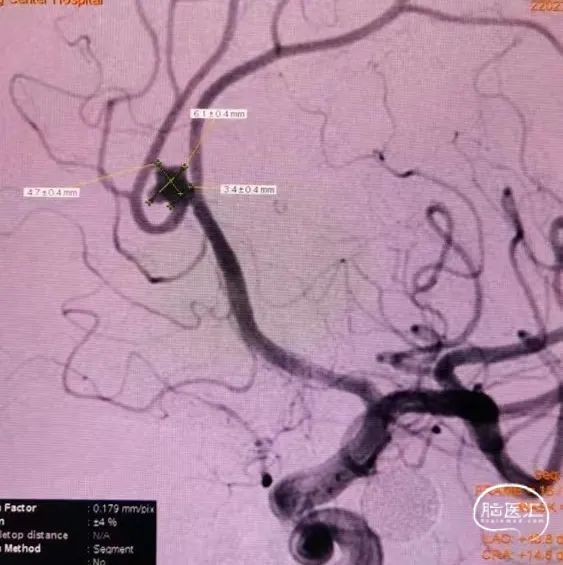

动脉瘤测量:

先通过微导管填塞成篮圈,输送支架到左侧大脑中动脉下干并释放,使支架覆盖动脉瘤开口。依次填入Jasper®SS弹簧圈多枚。

左侧大脑中动脉分叉部动脉瘤呈分叶状,有子瘤,破裂风险大,累及大脑中动脉上下干,且动脉瘤形态不规则,需分区填塞。填塞使用的Jasper®SS弹簧圈圈体柔软,在瘤内钻缝能力强,能够很好地达到填塞效果,柔软性能强,基本不踢管,电解脱快速顺利,增加了手术的安全性及成功率。